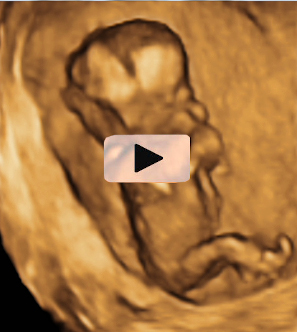

Ecografía Embarazo 2D y 3D Semana 12 - PRUEBAS DIAGNÓSTICAS